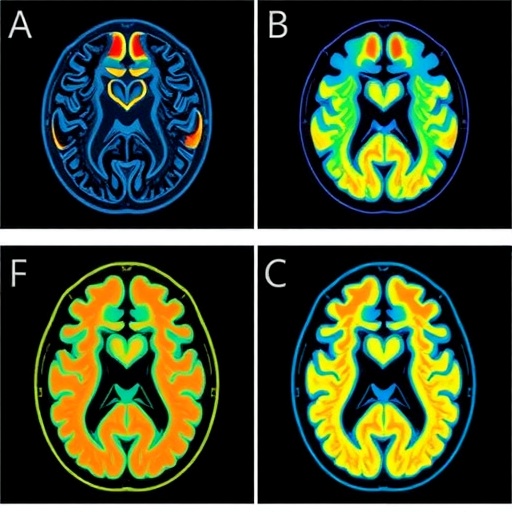

Leveraging advanced MRI perfusion imaging, the researchers pinpointed alterations in cerebral blood flow specifically within neural circuits governing emotion regulation and decision-making—two domains profoundly disrupted in depression. Areas such as the prefrontal cortex and anterior cingulate cortex, known for their involvement in mood modulation and cognitive control, exhibited distinctive perfusion patterns correlating with inflammation markers. These neurovascular imbalances potentially elucidate underlying mechanisms contributing to persistent depressive symptoms, including anhedonia and impaired reward processing.

Observing altered perfusion in reward-related brain regions offers a mechanistic explanation for anhedonia, a cardinal symptom often refractory to standard antidepressants. The diminished cerebral blood flow may reflect or precipitate synaptic and neuronal dysfunction, highlighting how systemic inflammation may translate into tangible brain circuit disruptions that sustain depressive syndromes. This neurological insight bridges peripheral immune status and central nervous system pathology.